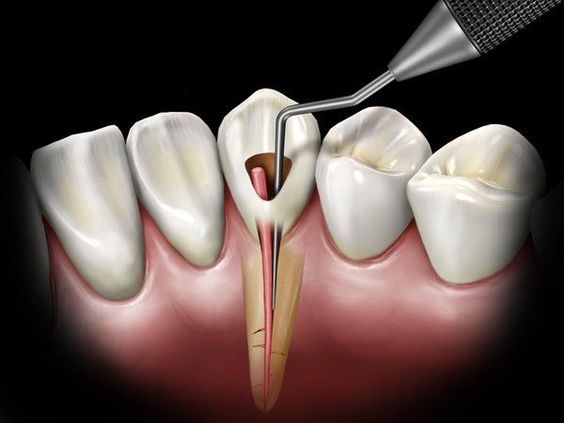

Endodoncia

Es la práctica odontológica que consiste en la extirpación de la pulpa dental y el posterior relleno y sellado de la cavidad pulpar con un material inerte.